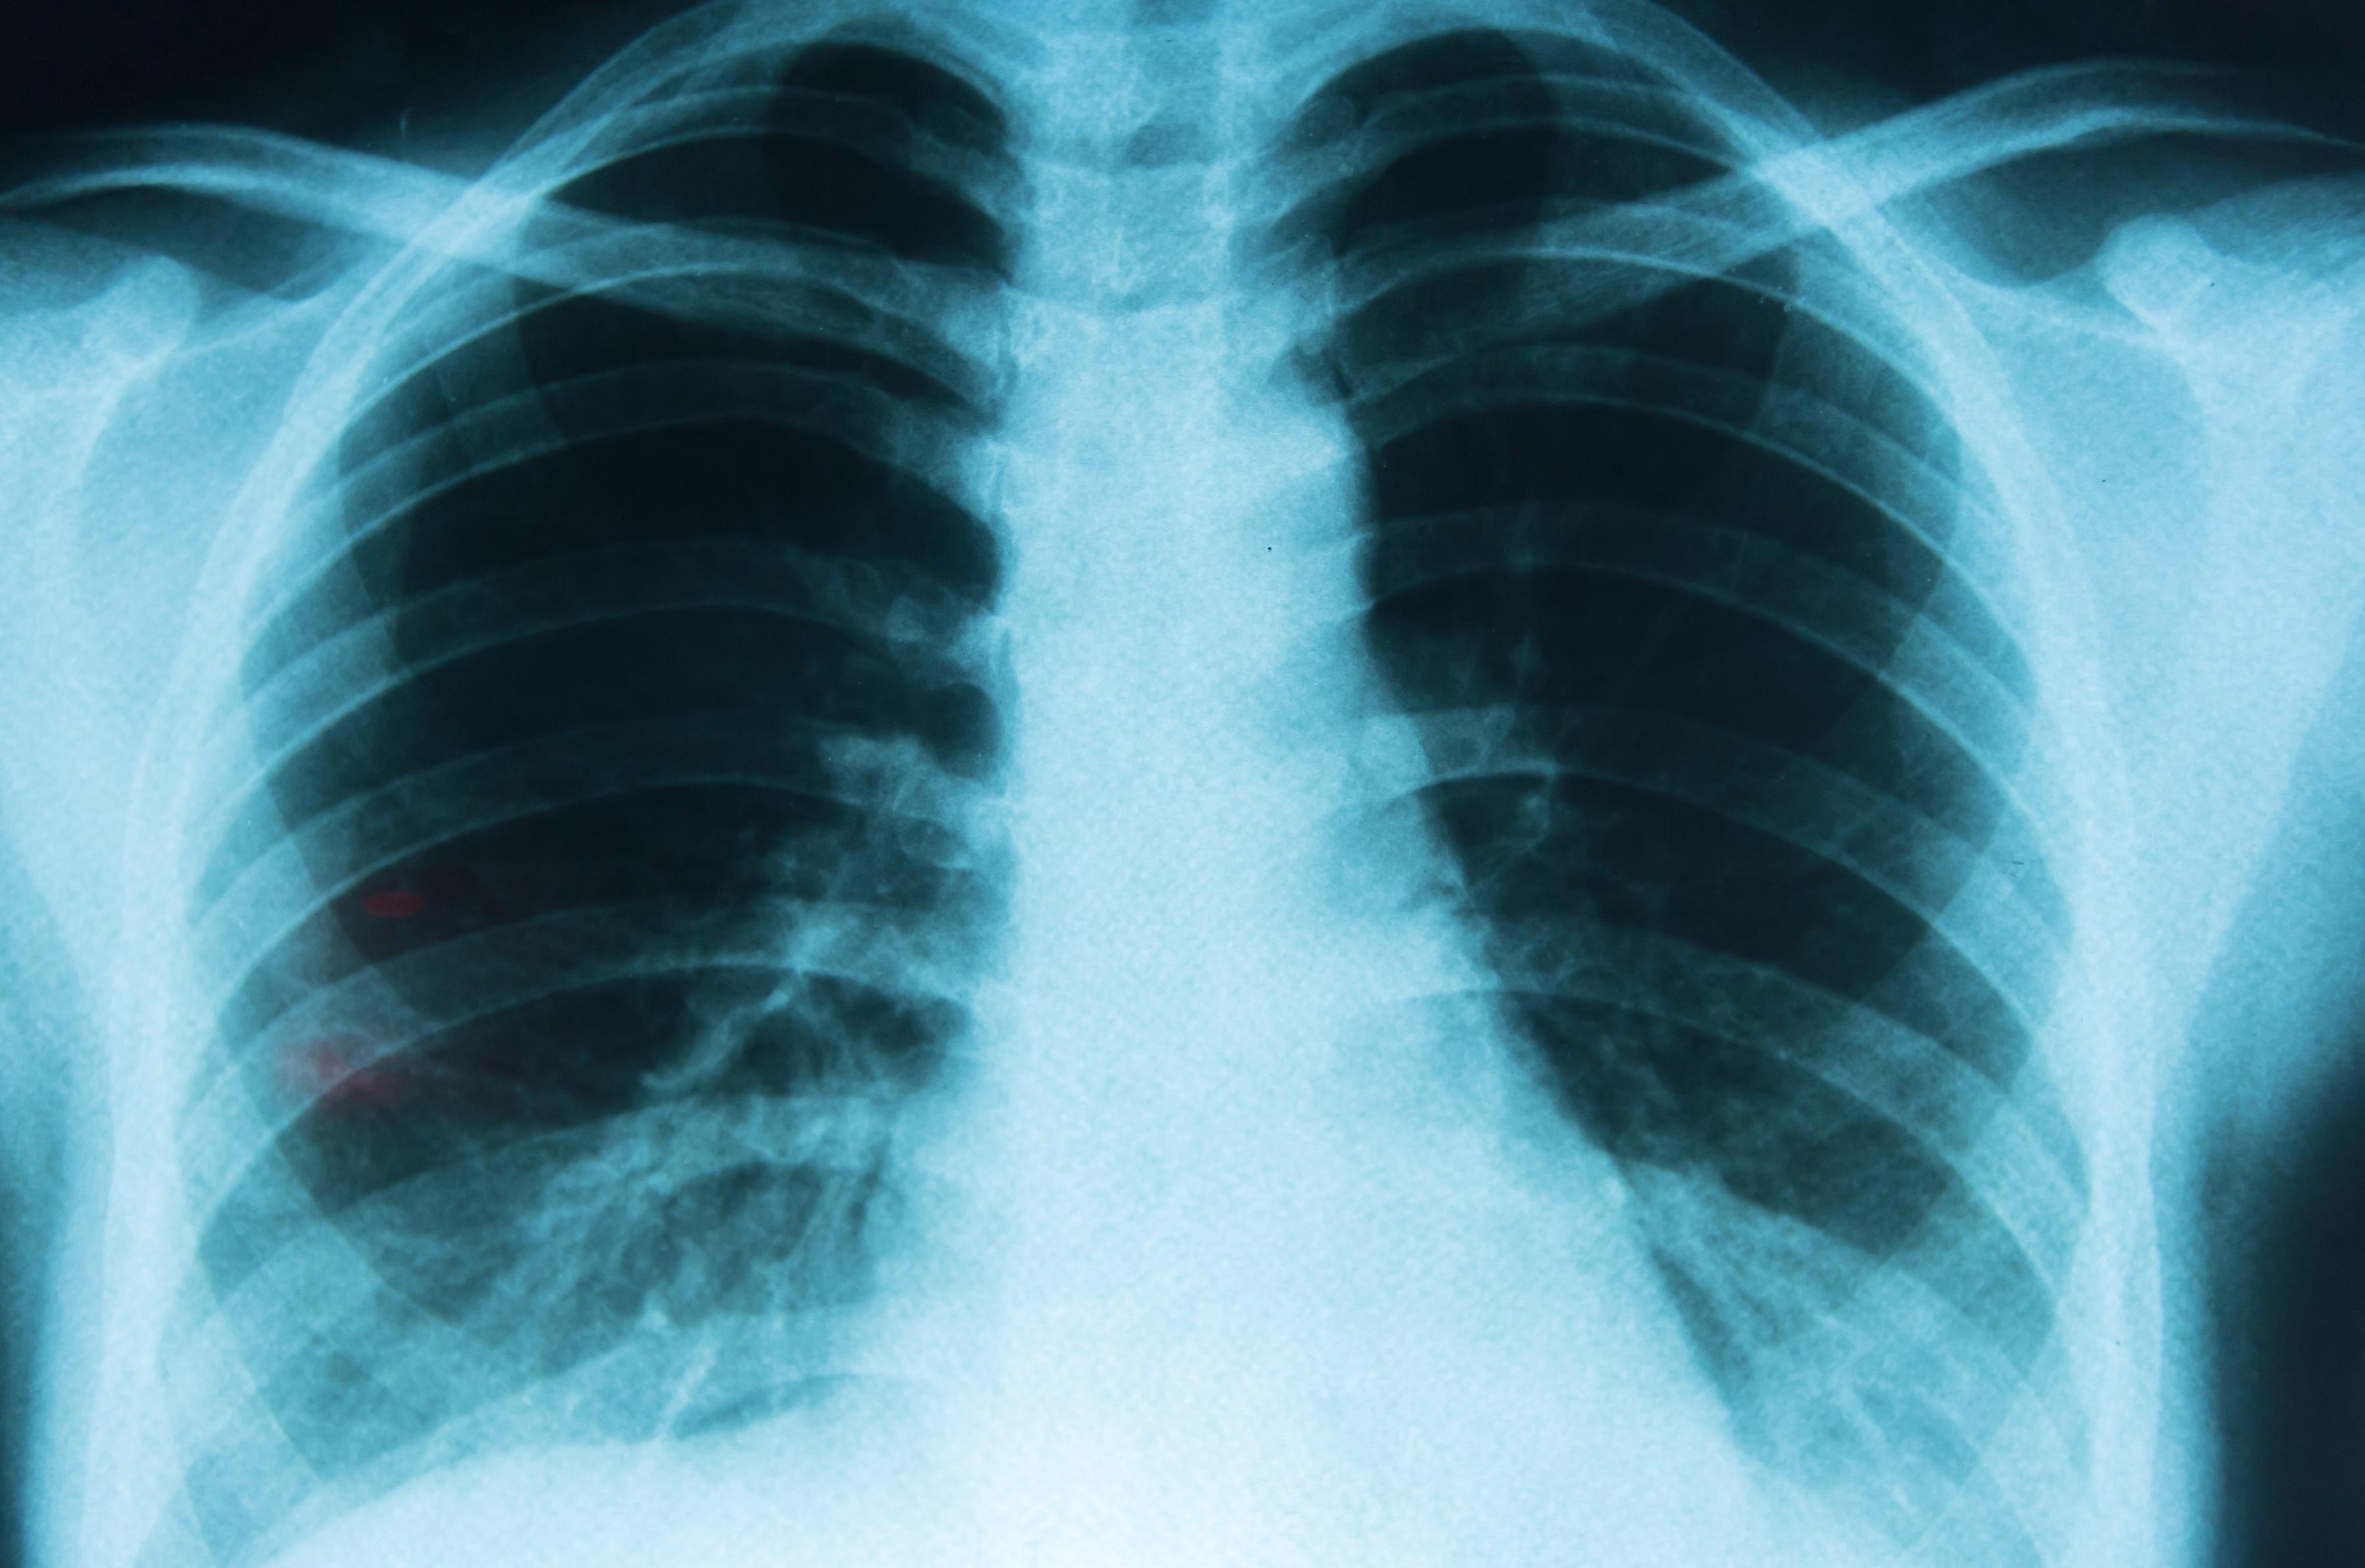

El cáncer de pulmón continúa siendo uno de los principales retos de salud pública a nivel global. Cada año se diagnostican más de 2 millones de nuevos casos en el mundo y se registran alrededor de 1,8 millones de muertes asociadas a esta enfermedad, de acuerdo con datos internacionales. A pesar de estas cifras, los avances médicos de la última década están cambiando de forma significativa las expectativas de vida de los pacientes.

Uno de los factores más determinantes en la supervivencia es la detección temprana. Cuando el cáncer de pulmón se identifica en etapas iniciales, la tasa de supervivencia a cinco años puede superar el 60%. Sin embargo, cerca del 70% de los casos todavía se diagnostican en fases avanzadas, cuando las opciones terapéuticas son más limitadas.

Los especialistas señalan que el tamizaje con tomografía de baja dosis en personas con alto riesgo, como fumadores o exfumadores mayores de 50 años, permite detectar tumores pequeños antes de que aparezcan síntomas. Esta estrategia ha demostrado reducir la mortalidad entre un 20% y un 30%.